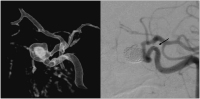

Abbildung 4: Breitbasiges Aneurysma der Arteria carotis interna links vor (links) und nach (rechts) endovaskulärer Behandlung mit Coils und Stent; der Pfeil zeigt die 4 Marker im kaudalen Stent-Ende.